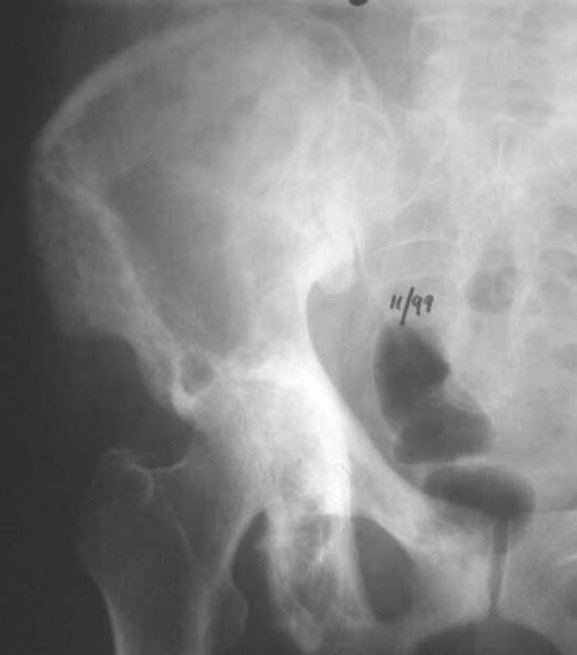

Imaging is critical in staging the condition:-